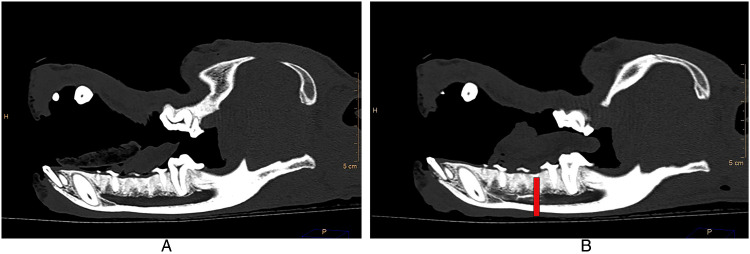

Awareness among veterinarians has increased regarding the need for comprehensive pain relief, but many companion animal veterinarians do not administer regional analgesia pre-emptively during dental procedures. The middle mental nerve (MMN) block desensitizes the ipsilateral mandibular incisor and canine teeth as well as soft tissues rostral to the delivery site. There is little published information on the efficacy of the MMN block in dogs. The objective of this study was to determine injectate distribution within the mandibular canal using a radiopaque contrast media/methylene blue solution. Half a milliliter of solution was injected within the opening of the middle mental foramen using a standard hypodermic syringe and a 25G x 25 mm needle. The course of the injectate was traced both via computed tomography (CT) and, in some cadavers, gross dissection. Post-treatment CT revealed that in 90% of the cases, the contrast diffused at least as far caudally as the mesial root of the third premolar tooth. The injectate was not identified within the canal of 5% of cadaveric mandibles examined. Although the solution used diffused caudally within the mandibular canal when injected using recommended clinical techniques, this may not completely represent the extent of clinical effects experienced in live patients. This technique also confirmed that the needle does not need to be advanced into the mandibular canal to achieve adequate diffusion to at least the mesial root of the third premolar tooth.